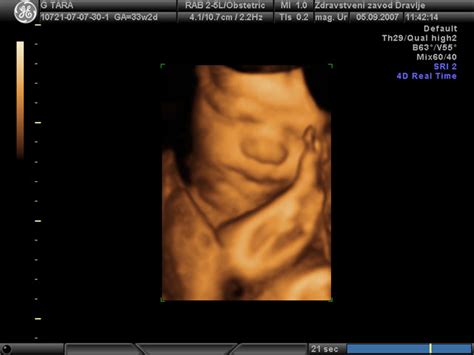

- Ultrazvočni pregled nuhalne svetline in zgodnje anatomije ploda (11.-14. teden): Ključen za presejanje na kromosomske nepravilnosti. Pregled rasti ploda, meritev nuhalne svetline, pregled nosne kosti in drugih markerjev.

- Drugi ultrazvočni pregled (okoli 20. tedna): Morfološki pregled ploda, ocena njegovega razvoja, organov, rasti, količine plodovnice in lege posteljice.

- Tretji ultrazvočni pregled (19.-23. teden): Podroben morfološki pregled, kjer se ugotavljajo ustreznost plodovega razvoja, morebitne nepravilnosti, rast, količina plodovnice, struktura in lega posteljice.